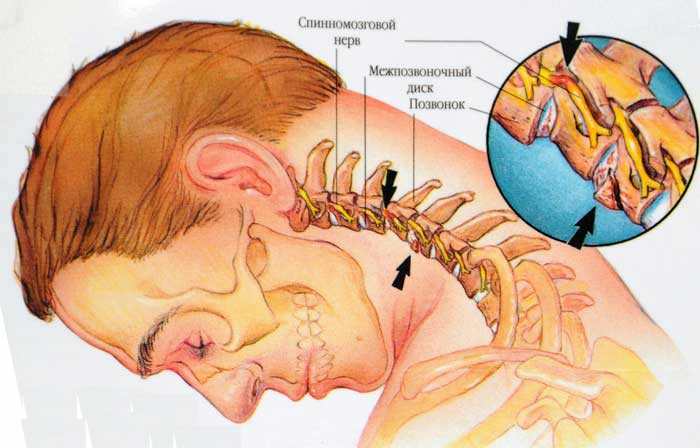

- подвывихи шейных позвонков и спондилолистез (вызывают деформацию позвоночного канала);

- остеохондроз (костные разрастания начинают сжимать артерию);

- окостенение, затрагивающее мембрану между позвоночником и затылком;

Серьёзные изменения затрагивают область костного канала и артерии, которая в него впадает. При гипоплазии ткани головного мозга получают значительно меньше крови, что может привести к негативным последствиям.